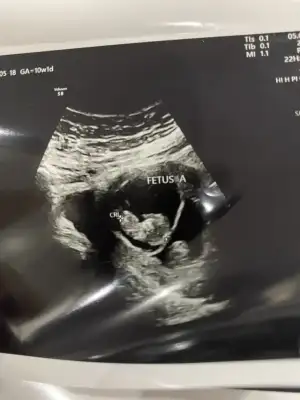

Ben dayanamadım gittim bugün ikiside o kadar güzeldi ki hareketli kıpır kıpır sırf onları öyle görebilmek için attım kendimi hastaneye 🥹 bebek olmuşlardı ellerini ayaklarını gördüm ikiz olduğu için ne nubu belli ne kafası zor ölçtü biri bize dönüktü zaten büyük olan fena olucak belli 😂 ama alt alta sağ tarafımda ikiside ben hep solum da da hissetmiştim ilk zamnlar ama bugün dikkat ettim alt alta ve sağa baktı hiç sola geçmedi darısı bekleyenlerin başına olsun inşallah 🙏🏾

• IMG_4037.webp

IMG_4037.webp

24,2 KB · Görüntüleme: 92

Birisi erkek(sağdaki) diğerini anlayamadım canım. Mucize gibiler 🥹 büyümüşler de, sağlıkla gelsinler🙏

Teşekkür ederim yorumun için canım 😍 evet böyle görünce içim bi rahatladı çok şükür bide 12. Haftamı görüyüm hayırlısıyla 🥹 inşallah biri kız biri erkekdir 🤭